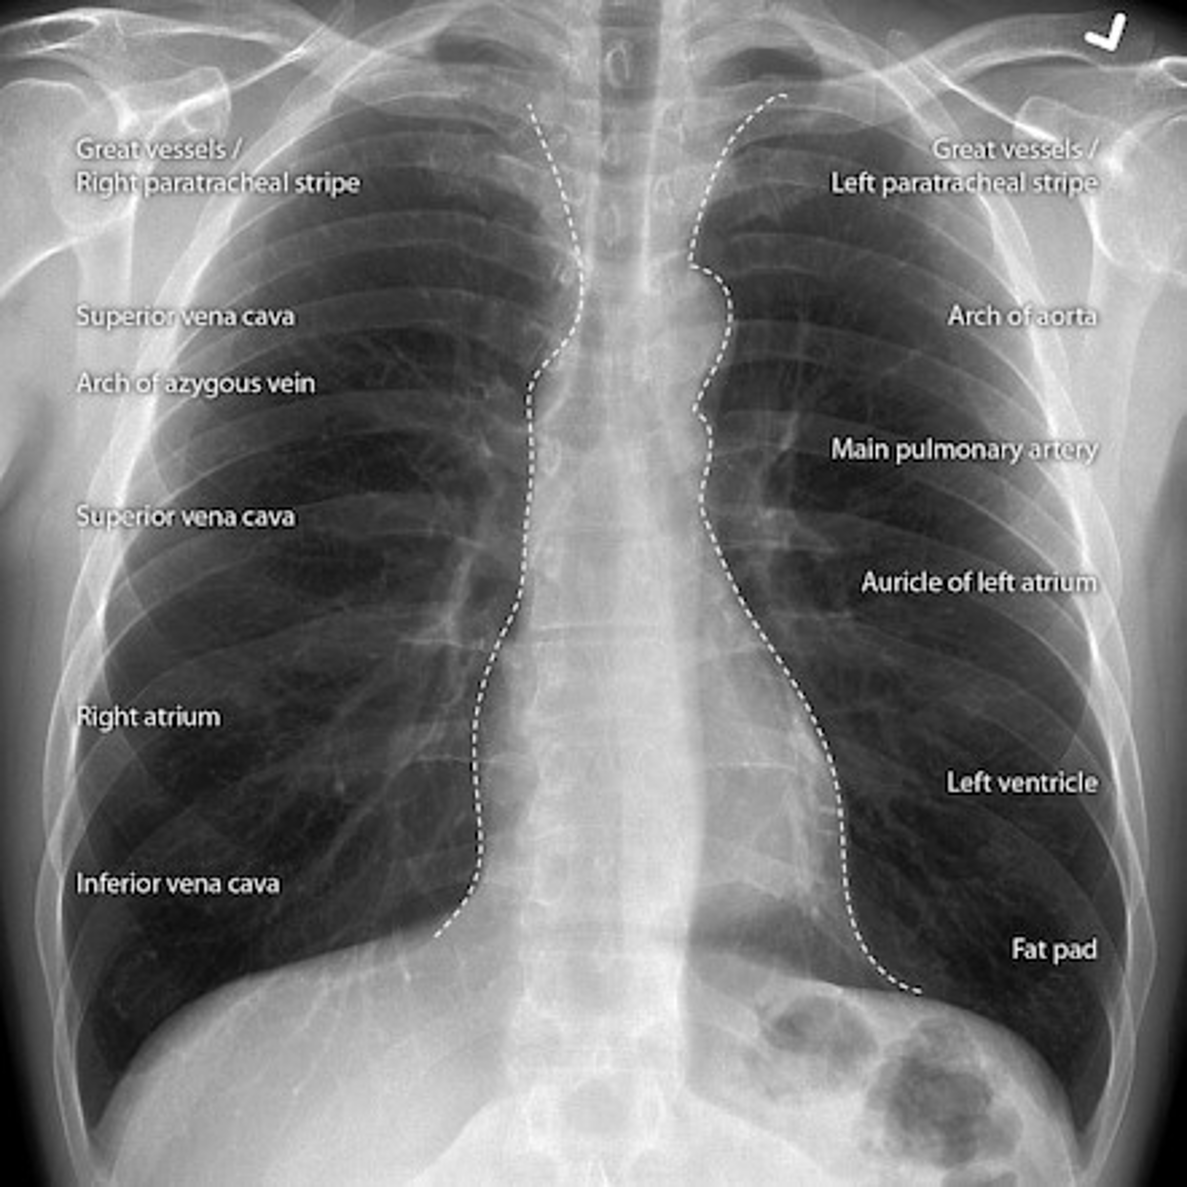

Name the mediastinal contours according to the numbers

1- superior vena cava

2- right atrium

3- inferior vena cava

4- aortic arch or knob

5- left pulmonary trunk

6- left pulmonary artery

7- left atrium

8- left ventricle

9- left cardiophrenic angle

Name the structures according to number